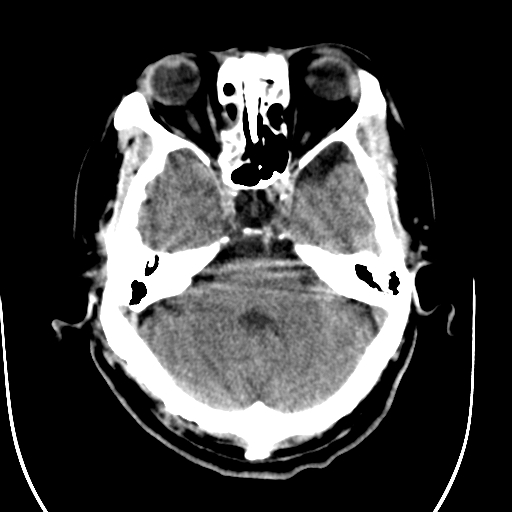

标题: CT28335:男,58岁,请各位看看是不是有脑积水,蝶窦内高密 [打印本页]

标题: CT28335:男,58岁,请各位看看是不是有脑积水,蝶窦内高密

轻度积水,蝶窦正常。

1)脑积水。2)副鼻窦炎。